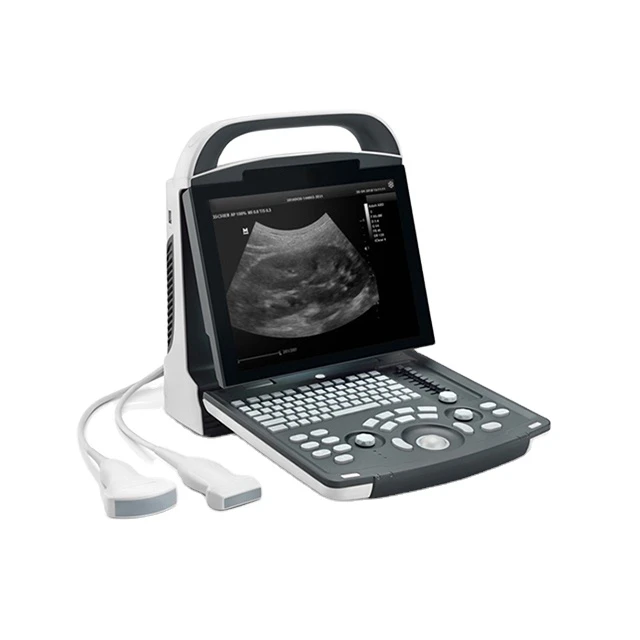

Portable Ultrasound Machine Mindray DP-10

12.1" LED Monitor

8-Segment

Light and compact

1 PCS

Abdomen, OB, GYN, Cardiology, Urology, Vascular

320Gb

Black and white